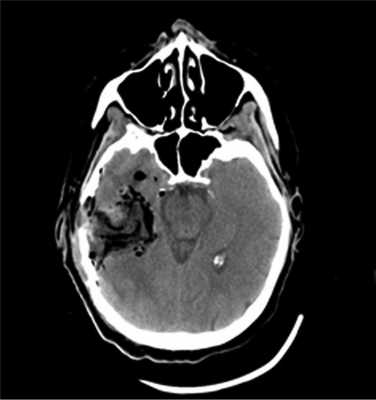

Опухоль, оказавшаяся при гистологическом исследовании глиобластомой (Grade IV), удалена 02.02.16. После операции пациентка была переведена в палату пробуждения отделения реанимации, где спустя 4,5 ч (через 2 ч после экстубации) развился вторичный генерализованный судорожный приступ продолжительностью около 2 мин. Приступ был купирован внутривенным болюсным введением диазепама 10 мг и вальпроевой кислоты (конвулекс) 500 мг. Экстренное КТ-исследование выявило послеоперационные изменения правой височной доли и отсутствие хирургических осложнений (рис. 2).

Рис. 2. Наблюдение 1. СКТ в 1-е сутки после удаления опухоли правой височной доли. Выявлены послеоперационные изменения в зоне хирургического вмешательства.